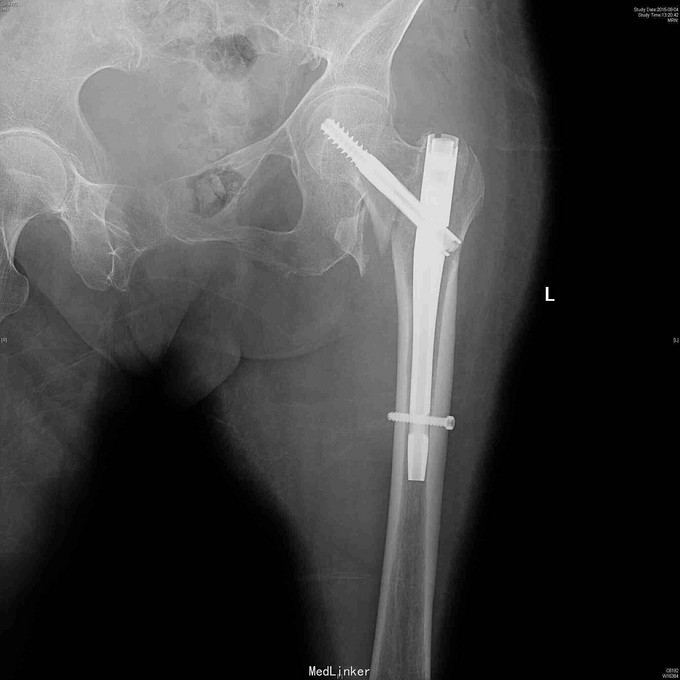

诊断:左股骨粗隆间骨折 治疗:左股骨粗隆间骨折闭合复位髓内钉固定术。术后抗凝4周,预防骨质疏松治疗。

随访:8周后复诊,左髋无明显不适,屈髋自如,已部分负重行走。 讨论:股骨粗隆间骨折最佳治疗方法是闭合牵引复位近端髓内钉固定,预后都不错。对于老年人,骨质疏松明显,容易发生腰椎,髋关节和桡骨远端等部位的骨质疏松压缩骨折,所以术后应当重视骨质疏松方面的治疗并坚持。一起讨论一下该例手术存在的不足和治疗老年人骨折方面的经验。